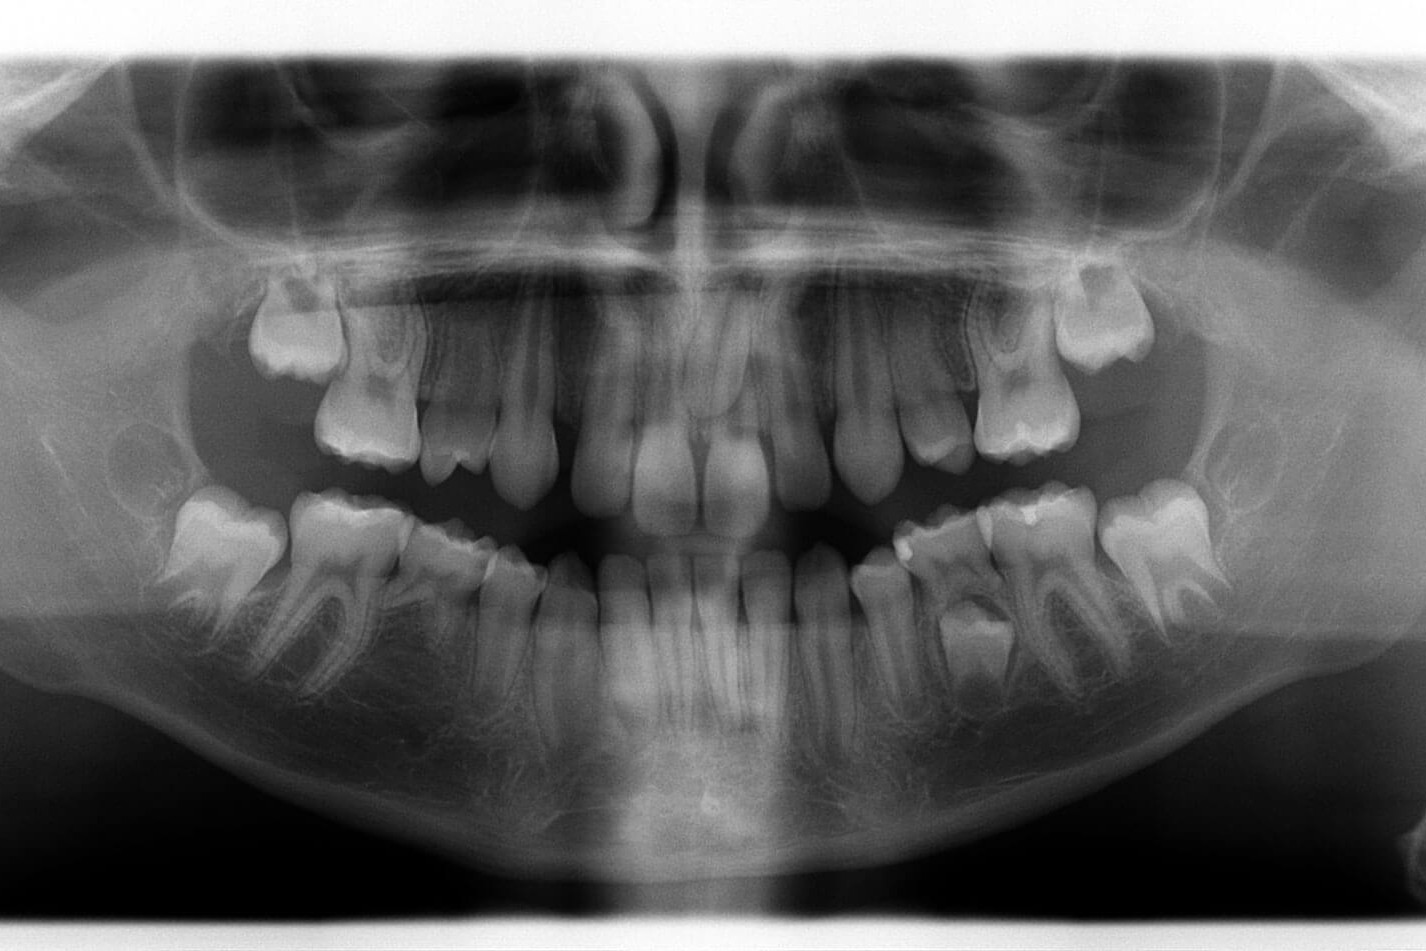

- Diagnosi precoce della carie mediante transilluminazione laser

- Valutazione del rischio di carie basso, moderato ed alto

IMPLANTOLOGIA

Il tuo miglior investimento.

- Per sostituire uno o più denti

- Anche con innesti ossei o rialzo di seno mascellare